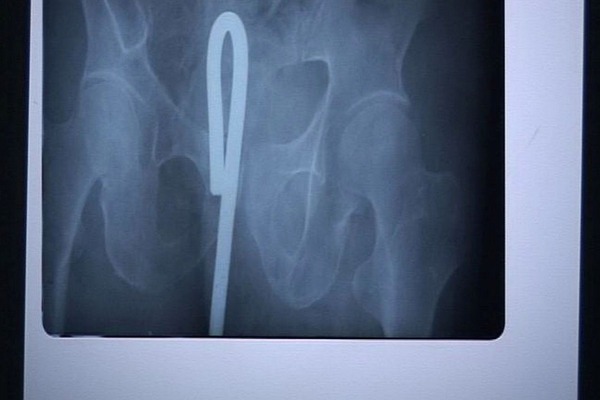

同じマンガで、アソコが痛いと主婦がやって来て、レントゲン撮ったら編み物に使うかぎ針が。なんで?と混乱する主婦…が、そう言えば学生の頃にオ〇二ーしててかぎ針使ってて抜けなくなり、そのうち出てくるとほっといて忘れてたって…。

10年は異物入れたまま、夫婦生活もしてたって…わからんかったんか?って話もあった。

「うわぁ」と思った数年後、テレビ見てたらその女がミスコンで優勝しててビックリした…って話をむかしマンガで読んだ。